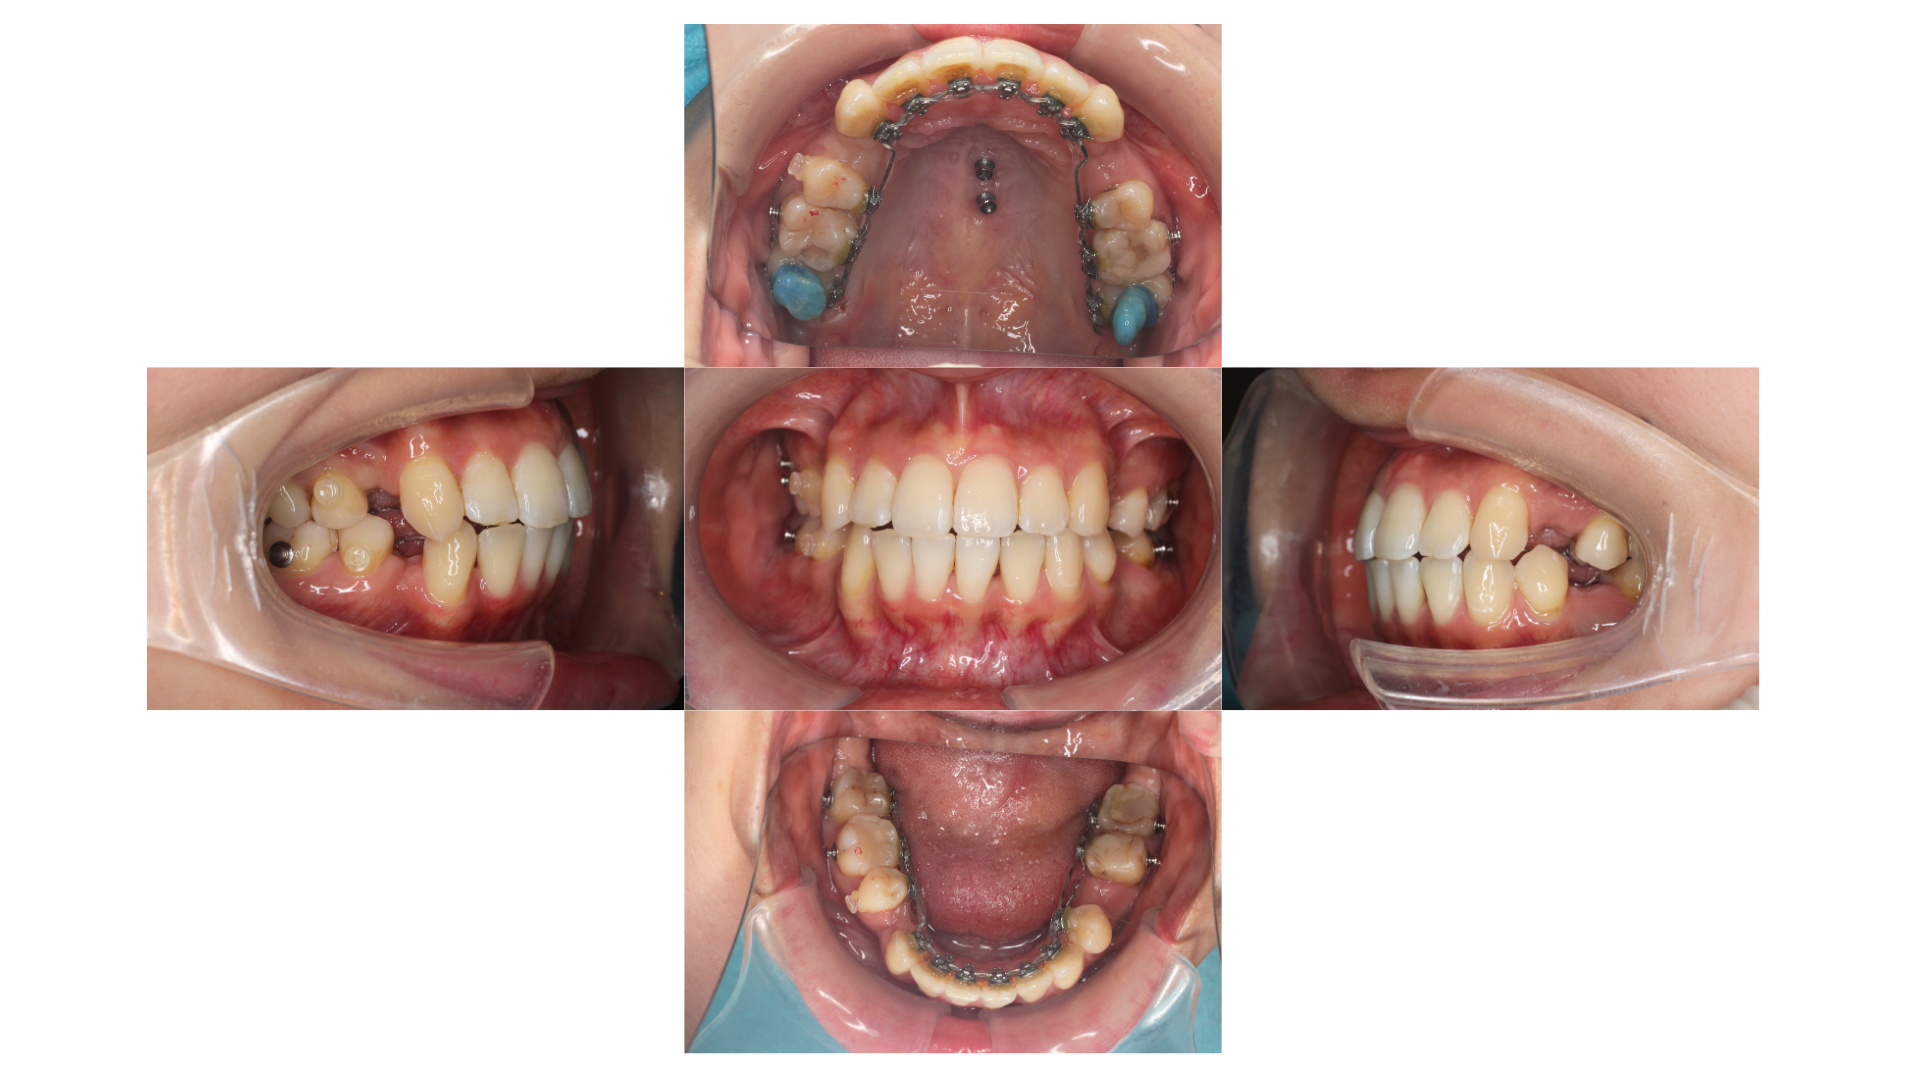

装置装着時